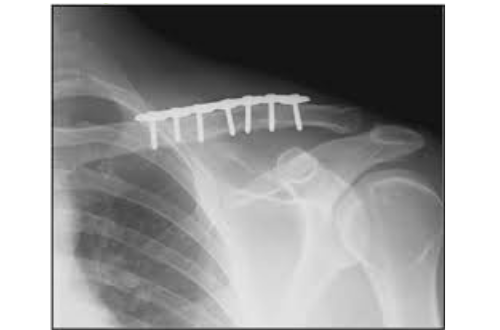

Mổ nắn và bất động bên trong: Đây là phương pháp thường được sử dụng trong điều trị phẫu thuật xương đòn. Sau khi mở ổ gãy nắn chỉnh các di lệch, xương gãy được bất động bằng các kim loại đặc biệt như đinh nội tủy, nẹp vít.

Nẹp vít:

• Sau khi mổ nắn hết các di lệch xương gãy. Các mảnh xương được cố định bằng nẹp và ốc vít đặc biệt. nẹp được đặt mặt bên ngoài của xương. Sau phẫu thuật bệnh nhân có thể có cảm giác tê bì một vùng da ở dưới vết mổ, nhưng cảm giác tê bì sẽ mất dần theo thời gian.

• Vì xương đòn nằm sát dưới da nên bạn có thể sờ thấy nẹp ốc qua da, đa số nẹp ốc không cần phải lấy ra sau khi xương lành trừ khi chúng gây ra những cảm giác khó chịu cho bệnh nhân.

Xquang sau mổ kết hợp xương đòn bằng nẹp vít.